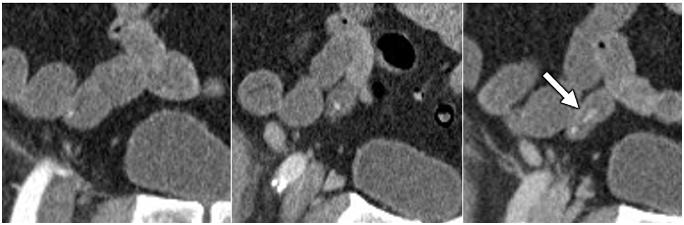

CT Enterography (uses oral contrast). Technique: CTE should be performed using multiphase technique in patients older than 40 years of age where vascular lesions are a common cause for bleeding.